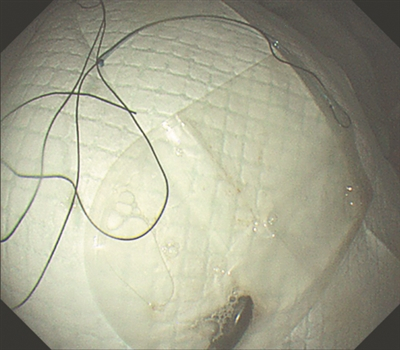

标本袋“套”出的磁铁。

胡健聪尝试用异物钳、圈套器等常规取异物器械,发现都没有办法把磁铁夹住取出。他立即联系手术室,借用手术室腹腔镜常用的无菌标本取出袋,在袋子上绑上丝线,再通过胃镜把标本袋带入胃腔,通过异物钳慢慢像“包饺子”一样把磁铁推入标本袋,最后牵拉丝线经过嘴巴终于把磁铁完整取出。